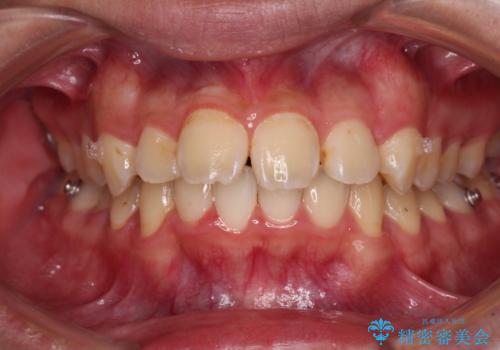

また、左右の犬歯の位置関係は上顎歯列が前方に位置する咬み合わせとなっており、インビザライン単体で治療するよりは、ワイヤー装置や補助装置を併用した方がより良い仕上がりになることが期待されました。

来院時は学生であったので、補助装置により上顎臼歯を後方に移動させ、下顎歯列はワイヤー装置による傾斜を改善させ、就職のタイミングでインビザラインにて仕上げていくこととしました。